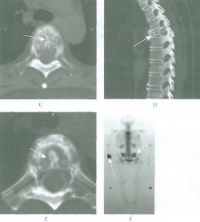

二CT:

1.骨囊肿一般多呈圆形、卵圆形低密度骨质缺损,边缘清晰,无硬化。

2.局部骨皮质变薄呈囊性膨胀。

3.少数囊肿内可见骨性间隔,呈多房改变。

4.骨囊肿内的CT值多为水样密度,有出血时密度可升高。

5.增强扫描囊肿不强化。

三MRI表现

1.多发在长管骨的干骺端,病灶呈圆形或椭圆形,其长轴与长骨纵轴一致。

2.病灶于T1WI上多呈低或中等均匀信号,T2WI呈明显均匀高信号,若囊液内有出血或含胶样物质则T1WI和T2WI上均呈高信号,少数呈多房改变时T2WI上可见低信号纤维间隔。

3.病灶周边骨壳呈圆圈样低信号,一般完整,边缘清晰。局部骨皮质变薄,无骨膜反应。常伴发病理性骨折,表现为骨皮质断裂,骨片陷落而插入病灶内,称之为骨片陷落征(fallenfragmentsign),此征在T2WI上显示较清晰即在高信号的囊液中见低信号的骨片线条影。

4.增强扫描:病灶不强化。